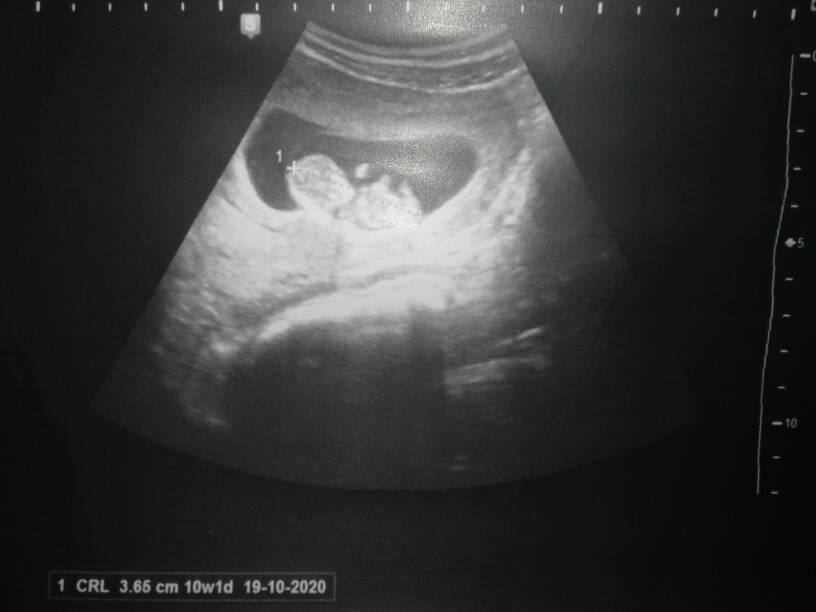

Pewnie dlatego masz takie ładne zdjecie na którym widać że to mały człowiek. Ja miałam przez brzuch ale pewnie przez te moje sadło takie byle jakie to zdjęcie [emoji853] oby z prenatalnych było już konkretne bo nawet nie mam sie czym chwalić.

No leżała sobie małpa wygodnie na pleckach, to ją akurat złapał[emoji23]